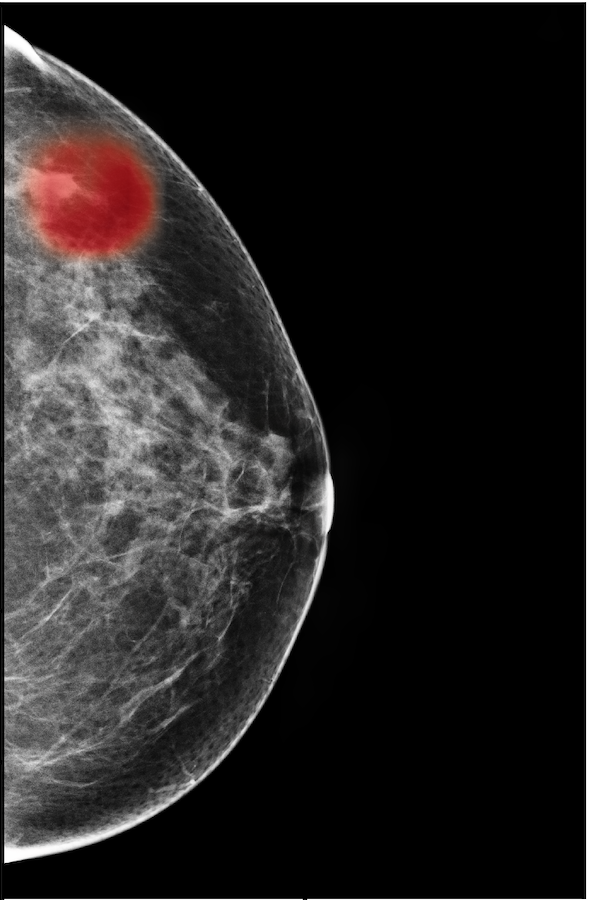

Screening mammography is inherently different from typical natural images from a few perspectives. First of all, as illustrated in Figure 1, regions of interest (ROI) in mammography images, such as masses, asymmetries, and microcalcifications, are often smaller in comparison to the salient objects in natural images. Moreover, as suggested in multiple clinical studies [72, 53, 73], both the local details, such as lesion shape, and global structure, such as overall breast fibroglandular tissue density and pattern, are essential for accurate diagnosis. For instance, while microcalcifications are common in both benign and malignant findings, their presence in a ductal distribution, such as in the third example of Figure 1, is a strong indicator of malignancy. This is in contrast to typical natural images where objects outside the most salient regions provide little information towards predicting the label of the image. In addition, mammography images are usually of much higher resolutions than typical natural images. The most accurate deep CNN architectures for natural images are not applicable to mammography images due to the limited size of GPU memory.

The NYU Breast Cancer Screening Dataset [78] includes 229,426 exams (1,001,093 images) from 141,472 patients.222Our retrospective study was approved by our institutional review board and was compliant with the Health Insurance Portability and Accountability Act. Informed consent was waived. Each exam contains at least four images which correspond to the four standard views used in screening mammography: R-CC (right craniocaudal), L-CC (left craniocaudal), R-MLO (right mediolateral oblique) and L-MLO (left mediolateral oblique). An example is shown in Figure 3.

For all exams matched with biopsies, we asked a group of radiologists (provided with the corresponding pathology reports) to retrospectively indicate the location of the biopsied lesions. This way we obtained the segmentation labels: where if pixel belongs to the benign/malignant findings. An example of such a segmentation is shown in Figure 3. In all experiments (except for experiments in Section 3.6 that assess the benefits of utilizing segmentation labels), segmentation labels are only used for evaluation. We found that, according to the radiologists, approximately of exams were mammographically occult, i.e., the lesions that were biopsied were not visible on mammography, even retrospectively, and were identified using other imaging modalities: ultrasound or MRI.